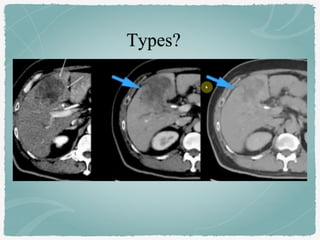

A)

B)

C)

D)

Acute interstitial pancreastitis: Normal enhancement

of the entire pancreas with mild surrounding fatty

infiltration.

ANC. Necrosis of the pancreas.

Inhomogeneous collection in the peripancreatic

tissue. No wall.

Acute necrotizing pancreatitis.

The pancreas do not enhance.

APFC: fluid collection at tail of

pancreas with no wall